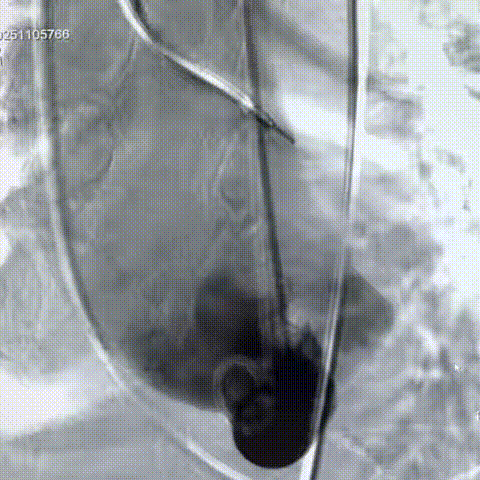

手术过程

手术过程:在右股动脉穿刺建立通路后,顺利送入大鞘,经食道超声及血管造影确认路径稳定。18mm球囊预扩后评估冠脉灌注良好,后将Prostyle A® AV26瓣膜精准释放于目标位置,超声显示无瓣周漏,术后即刻造影显示无明显反流,术前PGmean40mmHg,术后导管测平均跨瓣压差8mmHg,心功能明显改善,患者生命体征平稳。

最终造影形态位置良好,无瓣周漏